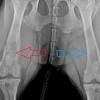

Our Dog Has Cancer And We Re Not Treating It Time from api.time.com For canine osteosarcoma, which is the most common type of bone cancer tumor in dogs, the treatment of choice is amputation of the affected limb, followed by chemotherapy. So when kristen constable and her family returned home from vacation and discovered their beloved greyhound limping, they assumed ruby had simply injured herself while playing. Lameness or a distinct swelling may be noted. Some pure breeds, such as golden retrievers and boxers. Multiple myeloma is an uncommon cancer that is derived from a clonal population of cancerous (malignant) plasma cells in the bone marrow. Osteosarcoma is the most common primary bone tumor of dogs and nearly 10,000 dogs are diagnosed with this cancer each year. Radiation is a common method for the palliation of bone cancer pain in human and animal cancer patients. Osteosarcoma is an aggressive, highly metastatic cancer that requires an aggressive treatment plan.

Case Study Canine Osteosarcoma from www.aaha.org Recognizing signs, understanding risk factors and knowing about treatment. The common treatment is chemotherapy, but it is rarely curative in dogs and has proved to mainly delay the recurrence of the cancer, bryan said. It begins as a tumor that often affects the long bones of the limbs, but it can affect any bones in the body. Osteosarcoma accounts for 85% of all primary malignant bone tumors of dogs and tends to affect the limbs more commonly than the spine or skull. Precision medicine treatment saves family pet. Ruby had always been an active dog. Palliative radiation is the second mainstay of the palliative treatment of appendicular osteosarcoma in dogs. Since the most common cause of death is not the tumor, but the spread of cancer to the lungs, chemotherapy is used to make sure that all of the cancer cells are killed (adriamycin (doxorubicin) and cisplatin or carboplatin).